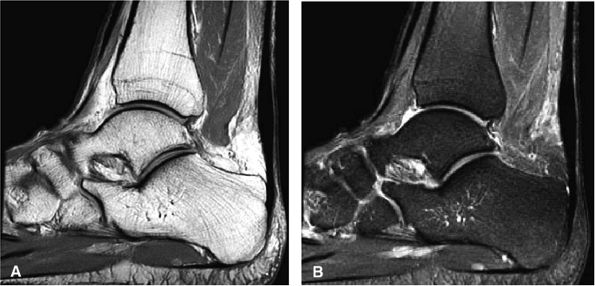

Achilles tendon rupture usually occurs 2 to 6 cm proximal to its os calcis insertion.

Sagittal images are used to identify the proximal and distal tendon ends.

Axial FS PD FSE images are used to confirm complete rupture (an intact plantaris may simulate an intact tendon in the sagittal plane).

-

Partial tears demonstrate hyperintense signal with incomplete anterior-to-posterior or posterior-to-anterior extension on FS PD FSE images.

Complete tears demonstrate a hyperintense fluid-filled tendinous gap.

Tendon rupture usually occurs 2 to 6 cm superior to the os calcis.

The size of the rupture varies, based on the degree of tendon retraction.

Ruptures demonstrate diffuse convexity of the anterior margin and enlarged tendon ends at the tear site.